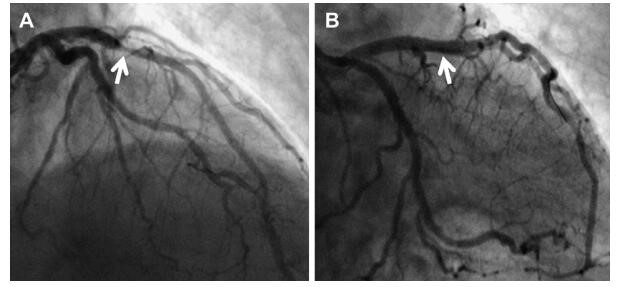

三、心肌梗死不放支架和搭桥,还能怎么治疗?

心肌梗死的治疗,如果是急性心肌梗死,最好的方法就是急诊溶栓或急诊介入治疗,但并不是每个心肌梗死都有机会急诊介入治疗,在我国急性心肌梗死的每年50万病例中,能够进行急诊介入手术的微乎其微,尤其可见,支架或者搭桥,并不是你想的那样,想做就能做。那么如果不做支架或者搭桥,心肌梗死还能怎么做呢?答案其实在第一个问题中已经给出,除了介入和手术以外,就剩下内科保守治疗了。